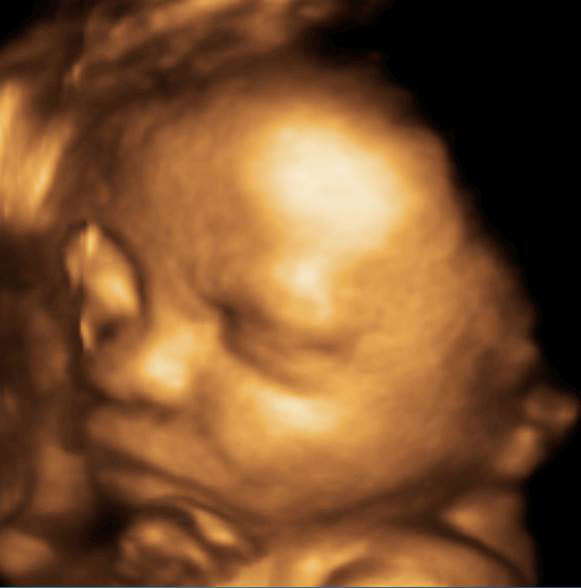

3D i 4D tehnologija omogućava da vidimo površinu bebe na lepši način i pokrete ploda u realnom vremenu.

Takođe nam omogućava da bolje vidimo fetalne mane na licu, šakama i stopalima.

Kao i 2D, 3D i 4D koriste ultrazvučni talas da se kreira slika bebe u materici. 3D je kreirana slika u prostoru dok 4D prikazuje pokret unutar materice pa možemo videti kako se beba smeje, mršti ili zeva.

Da bi se dobile dobre slike poželjno je da se pregled radi između 24 i 32 nedelje trudnoće.